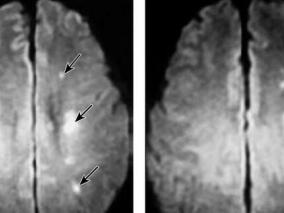

1小时条评论短暂性脑缺血发作(TIA)是指短暂并反复发作的视网膜或脑局部供血障碍,导致短暂性神经功能缺失。TIA后48小时内的缺血性卒中发病率为5%,90日内为10.5%[1,2]。因此及时正确评价和治疗TIA有重要的临床意义。现报告1例弥散加权成像(DWI)异常的经典TIA,并就其诊断...